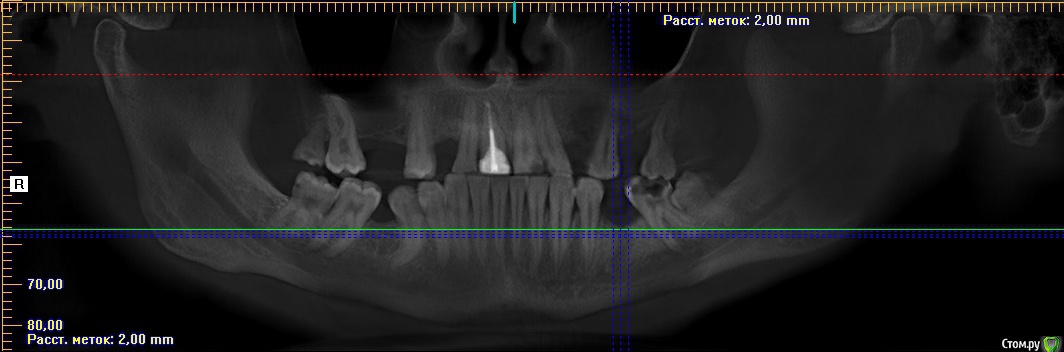

erm Опубликовано 2 февраля, 2016 Автор Поделиться Опубликовано 2 февраля, 2016 вот панарамный снимок 2014 года. второго зуба уже у меня нет, он был в 2015 удален Ссылка на комментарий

erm Опубликовано 2 февраля, 2016 Автор Поделиться Опубликовано 2 февраля, 2016 P.S 7-ка на данный момент тоже удалена, хот на снимке есть, просто снимки 14 года. летом удалили её, думали что это из-за нее Ссылка на комментарий